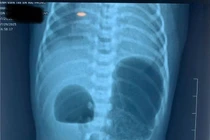

Bệnh nhi M.N., 28 ngày tuổi, được nhập viện tại Bệnh viện Nhi Hà Nội trong tình trạng thở dốc, lõm ngực và thở rít. Bé được chẩn đoán viêm phổi, sau vài ngày điều trị, các biểu hiện của viêm phổi đã cải thiện nhiều, nhưng bé vẫn còn biểu hiện thở rít, khó thở đặc biệt khi nằm ngửa, bé được chuyển sang khám chuyên khoa Tai Mũi Họng.

Tại đây, các bác sĩ đã tiến hành nội soi và phát hiện một khối bất thường, to căng tròn chiếm gần hết vùng họng của bé. Khối này đè ép vào thanh quản, gây ra những cơn khó thở nghiêm trọng.

Các bác sĩ chẩn đoán bé bị u nang hố lưỡi thanh thiệt – một loại u nang hiếm gặp ở trẻ sơ sinh. Bệnh lý này gặp chủ yếu ở người lớn hoặc trẻ lớn do tắc tuyến tiết nhầy ở hố lưỡi thanh thiệt, nhưng ở bé M.N., khối u lại có kích thước khổng lồ, là một ca bệnh đặc biệt.

Với cách tiếp cận toàn diện, các bác sĩ Tai Mũi Họng khoa Liên chuyên khoa, Bệnh viện Nhi Hà Nội đã loại trừ các bệnh liên quan, phối hợp với khoa Gây mê để thực hiện phẫu thuật. Mặc dù là bệnh nhi sơ sinh rất nhỏ, phẫu trường hẹp, khó thao tác nhưng ekip đã phẫu thuật thành công cho bé.

Sau mổ, bé đã hết hẳn các triệu chứng khó thở, thở rít. Nhờ việc chẩn đoán đúng và phối hợp kịp thời, sau phẫu thuật bé M.N đã ổn định sức khỏe và dự kiến sẽ sớm được xuất viện.